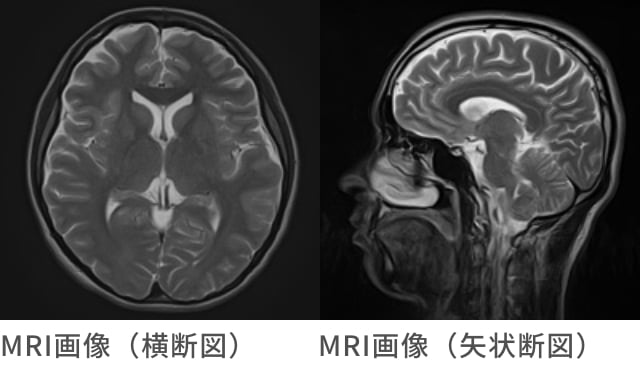

MRI検査

MRI検査とは

MRl検査は、CT検査と同様に体の断面を画像化する検査で、CT・MRlそれぞれの特長を活かし、目的とする臓器や検査内容により使い分けることで非常に高い精度の検査が可能となっています。

CT検査は、X線を使って断面像を得るのに対し、MRlは大きな磁石による”強い磁場”とFMラジオに使われているような”電波”を使って画像を得ることができるので、X線による被ばくがなく、CT検査と異なり、「横になったまま様々な方向からの断面像を得られること」、「組織間のコントラストに優れること」などの特長があげられます。

頭部MRl・MRA検査

脳卒中・脳腫瘍の早期発見に有効な検査です

現在、日本では年間に約13万人の方が脳卒中で亡くなっており、がん・心臓病などに次ぐ死因となっています。

脳卒中は、脳の血管に起こる病気の総称で、専門的には脳血管障害といい、大きく分けると血管が破れて起こる「脳出血」「くも膜下出血」、そして血管が詰まって起こる「脳梗塞」の3つに分けることができます。

頭部MRI・MRA検査は、それらの脳の病気を未然に察知し予防することを目的とした検査です。